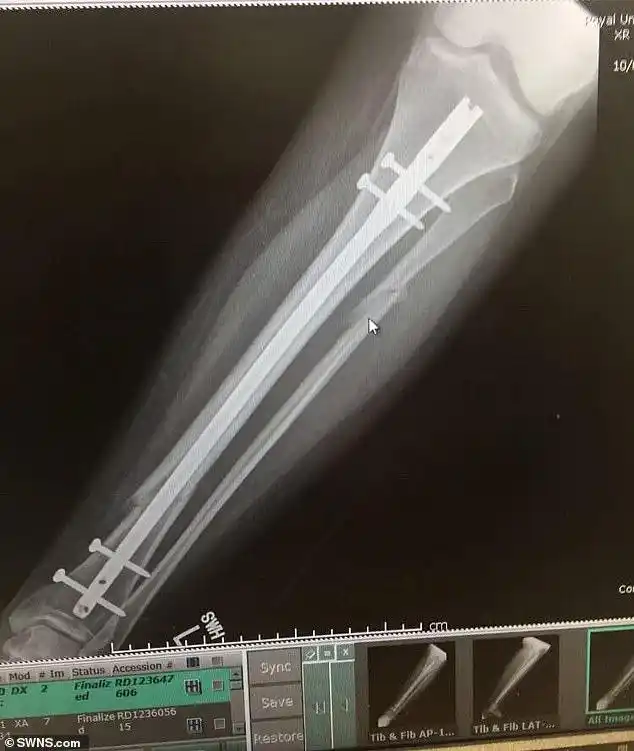

10岁女孩玩蹦床摔断腿 右腿被植入三颗钢钉 免责协议:由本人承担